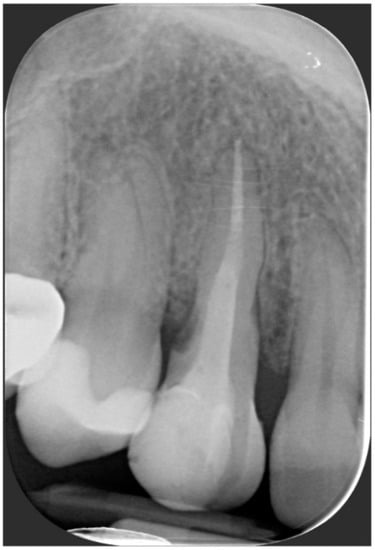

A 40-year-old patient presented with an endodontic fistula on the maxillary right canine (Figure 1a–c). Radiographic evaluation revealed internal root resorption (Figure 2). The medical history did not include any systemic conditions contraindicating implant placement or regenerative surgery. The patient did not suffer from any form of periodontal disease. Due to the extension of root resorption, the tooth was considered irrational to treat, and the treatment plan consisted of extraction and immediate implant positioning.

Figure 2. Radiographic evaluation revealing internal root resorption.